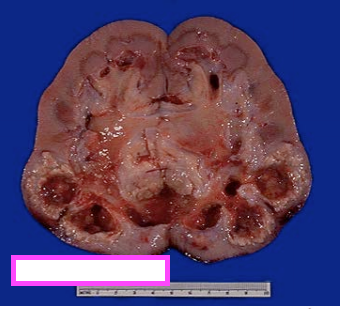

The lumen of the ureter is susceptible to constriction at 3 main sites, which are therefore prone to obstruction by renal calculi (stones):